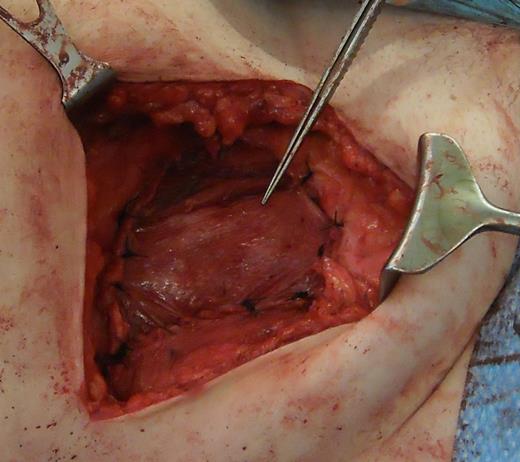

A 31-year-old man presented to his General Practitioner in May 2012 with a 6-week history of a painful mass in the right iliac fossa. There was no regional lymphadenopathy and hip examination was unremarkable. He was a smoker with a BMI of 33 and had undergone a right-sided inguinal hernia synthetic mesh repair in 2010. MRI with contrast confirmed a 6.9 × 6.7 × 4.6 cm mass invading the abdominal wall musculature (Fig. 4). Radiological features were suggestive of sarcoma or aggressive fibromatosis. Histology from an ultrasound-guided biopsy revealed aggressive fibromatosis. The patient opted for a surgical excision of the mass with abdominal wall reconstruction. The tumour was excised with the internal oblique, leaving the peritoneum and external ring cord structures intact. A 13 × 15 cm sheet of porcine intestinal biological mesh was used to repair the abdominal wall defect (Fig. 5). Inferiorly, the mesh was doubled over in the pre-peritoneal space to reconstruct the inguinal ligament, and sutured to the external oblique. The histology confirmed a final diagnosis of aggressive fibromatosis excised with 1 mm margins. At 24 months, there was good wound healing and no hernia, seroma or evidence of recurrence on follow-up MRI.

Depicting the use of porcine intestinal biological mesh to repair an anterior abdominal wall defect left by aggressive fibromatosis.